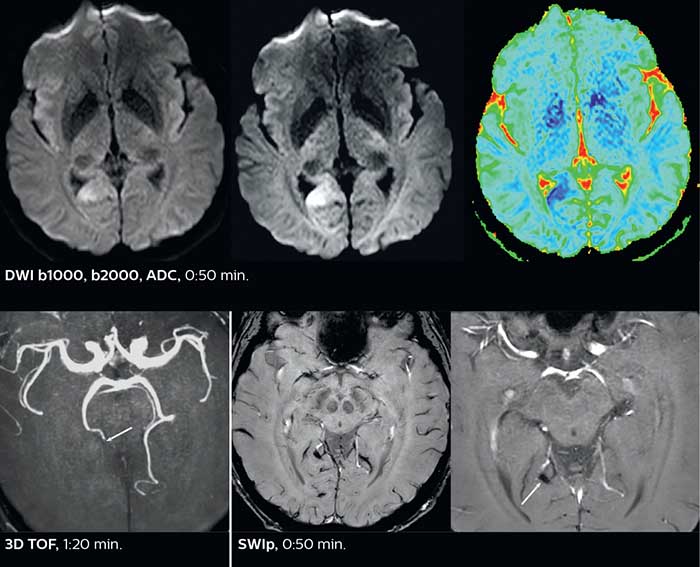

Fast acute stroke protocol

This is an example of acute ischemic stroke with distal occlusion of the right posterior cerebral artery. Note the improved visibility of the ischemic territory on the diffusion weighted image with high b-value. The 3D FLAIR shows a distal PCA occlusion. The fast SWIp depicts the thrombus on the isolated second echo image. The total scan time (including SmartBrain, preparations and a fast 3D T1w TSE Gd) is 8:00 minutes.

The ability to perform more sequences can help in making a swift and confident diagnosis. “For example, our stroke cases usually include the regular sequences that every center does (b1000 diffusion, FLAIR, time-of-flight angiography), but we also image supra aortic vessels, and we can replace a gradient echo sequence with a fast 50-second susceptibility-weighted sequence, and all of this doesn’t add much time. because all the regular sequences are accelerated on Elition.”

Improved diffusion imaging in stroke patients

Using MultiBand SENSE allowed the staff to improve their diffusion quality. “Our diffusion sequence was already fast before, about 40 seconds. Now with Elition, it still lasts 40 seconds, but we improved the spatial resolution by 0.2 mm and use high b-values to be more sensitive to visualize changes related to acute stroke,” says Dr. Savatovsky.